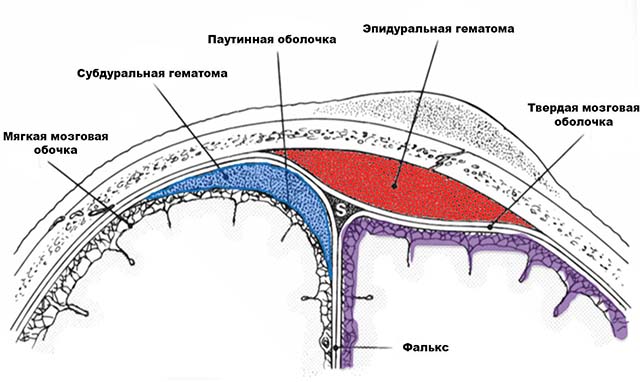

Гематома эпидуральная

Такие образования возникают из-за разрыва сосудов, находящихся между мозговой оболочкой и черепной костью. Если диагностирована эпидуральная гематома у новорожденного после родов, последствия ее довольно опасны. Уже через 5-7 часов в мозговых тканях может возникнуть существенное их сдавливание, вследствие чего состояние малыша стремительно ухудшается.

Гематомы субдуральные

При разрывах сосудов между мягкой и твердой оболочкой черепной коробки образуется гематома в голове после родов у новорожденного, которая называется субдуральной.

- кефалогематома – кровоизлияние в зону между надкостницей и костями головы;

- эпидуральная – кровяное скопление между костями черепа и твердой мозговой оболочкой;

- внутримозговая – проникновение крови в полость головного мозга;

- субдуральная – кровоизлияние в область между твердой и арахноидальной оболочками.

Эпидуральное кровоизлияние за счет нарушения целостности сосудов надкостницы возникает не между надкостницей и костью черепа, как кефалогематома, а между костью черепа и твердой оболочкой мозга. При этом последняя отслаивается от черепной кости.

2) Внутримозговая гематома — возникает, когда кровь из разорвавшихся сосудов проникает в головной мозг. Существует 4 типа внутримозговых гематом: внутримозжечковые, субдуральные, первичные субарахноидальные, интравентрикулярные и перивентрикулярные. Такая патология требует экстренного лечения, тактика которого зависит от степени тяжести патологии.

3) Епидуральная гематома считается наиболее неблагоприятной, так как у ребенка происходит разрыв артерии между твердой оболочкой мозга и костью черепа. Разрыв сосуда в таком случае возникает из-за перелома черепа. Массивное кровоизлияние приводит к тому, что кровь оказывает сильное давление на ткань мозга, а это становится причиной комы и летального исхода при несвоевременно начатом лечении. При эпидуральной гематоме проводится хирургическая операция.

4) Субдуральная гематома: кровь скапливается под твердой оболочкой мозга. Тактика лечения патологии зависит от степени ее тяжести. При небольшой субдуральной гематоме назначаются препараты для восстановления кровоснабжения мозга (Курантил, Эуфиллин). Крупная гематома требует хирургического лечения.